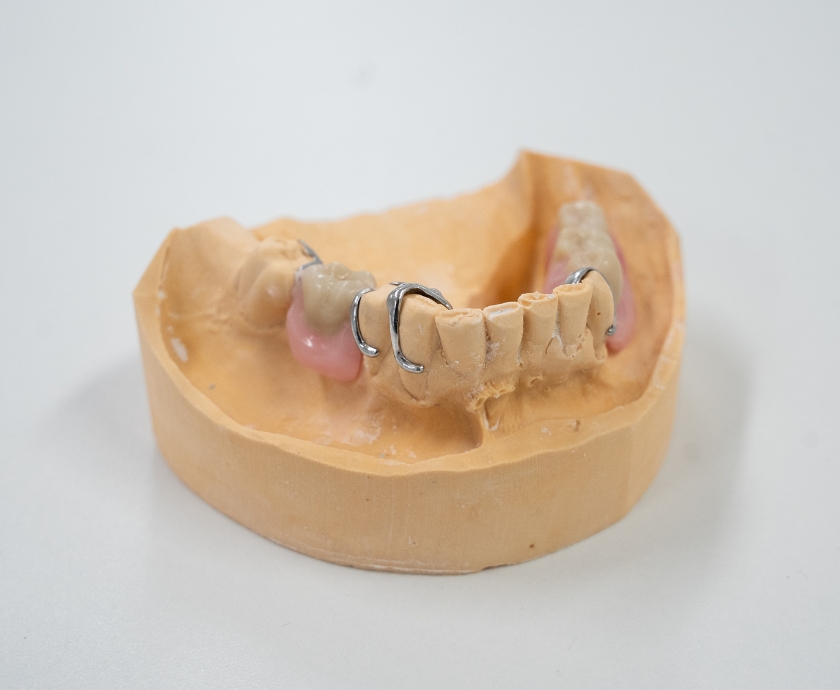

Een partiële prothese, ook wel bekend als een gedeeltelijk prothese of een plaatje, dient als vervanging voor één of meerdere ontbrekende tanden of kiezen in de mond. Deze prothese kan nodig zijn als tanden niet meer kunnen worden hersteld met een vulling, als een tijdelijke noodoplossing, als voorbereiding op een volledige prothese, of vanwege financiële overwegingen waarbij een brug of frameprothese niet mogelijk is. Gemaakt van tandvleeskleurig kunsthars, biedt het een esthetische oplossing met kunsttanden en -kiezen. Voor extra stabiliteit kunnen haakjes worden aangebracht die aan de eigen tanden worden bevestigd.

Een alternatieve optie is een frameprothese, ook een vorm van een gedeeltelijk gebit, maar met een metalen basis waar tandvleeskleurig kunsthars aan is bevestigd. Op deze metalen basis zijn metalen haakjes aangebracht, die rond de eigen kiezen worden geplaatst. Deze klammers worden speciaal gegoten naar de vorm van de kiezen, waardoor ze nauwkeurig passen. Welke van bovenstaande mogelijkheden voor u het meest geschikt is, verschilt per persoon. De keuze maakt u in overleg met uw behandelaar.